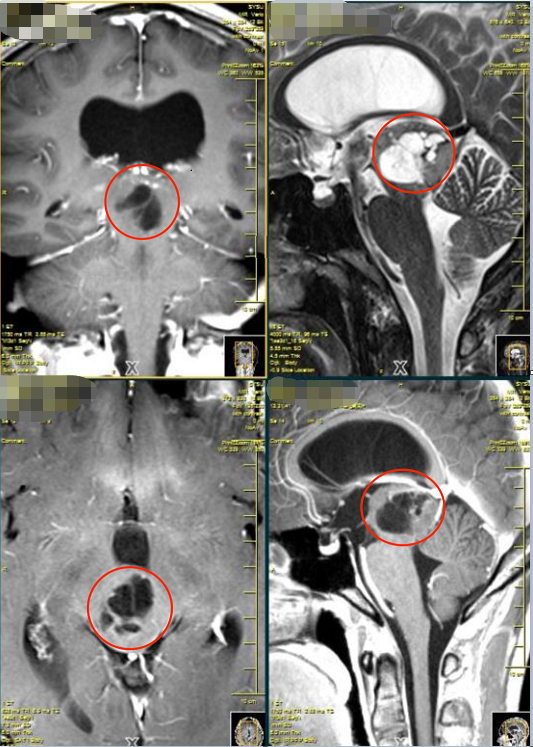

術(shù)前影像

MRI顯示這個(gè)血管畸形是新出血,每一次出血,可能都伴隨著癥狀的進(jìn)行性加重,危險(xiǎn)性會(huì)越來越高,神經(jīng)系統(tǒng)癥狀恢復(fù)也會(huì)更難。